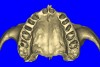

Using the interactive treatment-planning software application, the scan data was assimilated and both potential lateral incisor implant receptor sites were evaluated. It is a.combination of the data and the methodology used to interpret the data that is the basis for defining a new paradigm in diagnosis and treatment planning. Proper evaluation of these images and correct use of the interactive treatment-planning software tools is essential in creating a decision tree of treatment options. First, the data from the scan was reformatted into panoramic, axial, and cross-sectional images. The undistorted cross-sectional images revealed the residual alveolar bone in the area of the right lateral incisor. Then, a simulated schematic implant was placed within the bone with an abutment extension to help visualize the connection to the restorative position of the tooth (Figure 4A). The Triangle of Bone® (TOB), a concept developed by the author to analyze bone quality, quantity, and disposition at prospective dental implant sites using CBCT scans, aided in determining available bone volume by defining a “zone” for proper implant placement18,19 (Figure 4B).

Figure 4a  CT scan data was input into the treatment-planning software, which allowed (A) placement of a simulated implant and (B) the determination of the “zone” for proper placement.

Figure 4a

Figure 4b  CT scan data was input into the treatment-planning software, which allowed (A) placement of a simulated implant and (B) the determination of the “zone” for proper placement.

Figure 4b